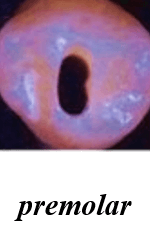

Shapes of the access cavity of all teeth

| Tooth | Access cavity shape | Average depth |

|---|---|---|

| Maxillary incisors | Triangular or oval (placed over the palatal surface) |

3-4 mm |

| Mandibular incisors | Triangular (placed over the lingual surface)

|

3-4 mm |

| Maxillary canines | Oval (placed over the palatal surface)

|

4-5 mm |

| Mandibular canines | Oval (placed over the lingual surface)

|

4-5 mm |

| Maxillary premolars | Oval or rounded (located over central part of the tooth)

|

4-5 mm |

| Mandibular premolars | Oval (over central of the tooth, slightly to the lingual)

|

4-5 mm |

| Maxillary molars | Trapezoidal (located over the mesial buccal cusp or the central part of the tooth)

|

5-6 mm |

| Mandibular molars | Trapezoidal or rhomboidal (centered over the mesial buccal cusp)

|

5-6 mm |

| Maxillary second molars | Trapezoidal (centered more mesially and palatally, slightly off-center) | 5-6 mm |

| Mandibular second molars | Trapezoidal or rhomboidal (centered over the mesial buccal cusp) | 5-6 mm |

| Maxillary third molars | Oval or trapezoidal | 5-7 mm |

| Mandibular third molars | Trapezoidal | 5-7 mm |